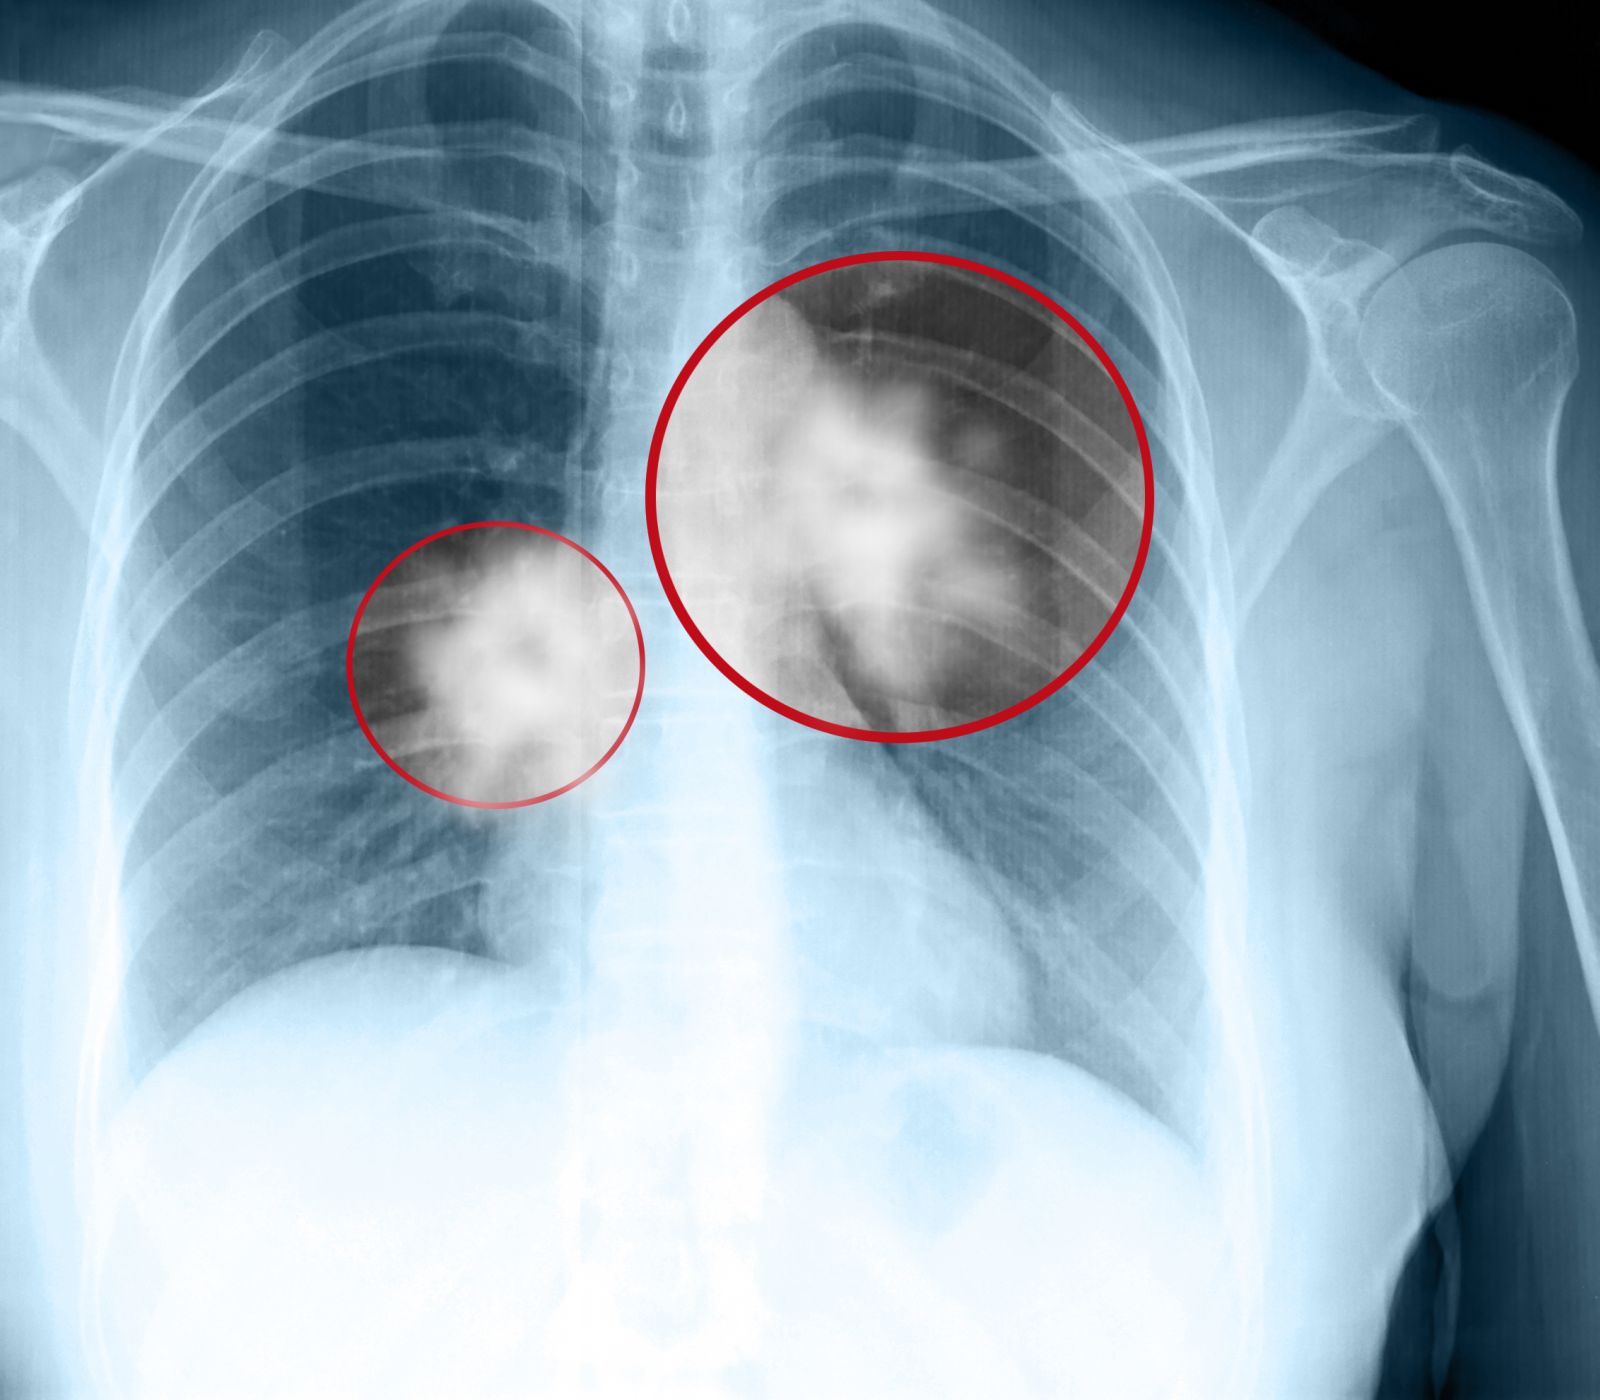

К сожалению, рак легких часто либо совсем не имеет ранних симптомы, либо имеет неспецифические ранние симптомы, которые люди часто не замечают. Около 25% людей с раком легких не наблюдают каких-либо симптомов, а заболевание диагностируется после рентгена грудной клетки или КТ во время обычной плановой проверки.

После того, как выявляется тип рака легкого, диагностируется его стадия. Стадия показывает, насколько рак распространился в организме (например, в лимфатические узлы или в отдаленные органы, такие как мозг). Этапы немелкоклеточного рака легкого отличаются от мелкоклеточного рака легкого.